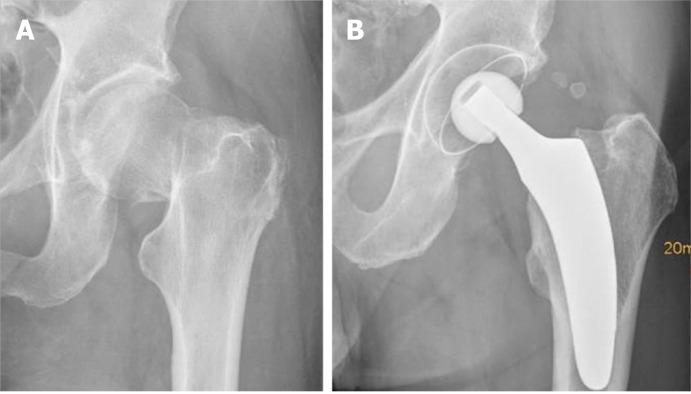

Short stems in total hip arthroplasty (THA) are becoming increasingly popular. In Germany, already 10.4% of all primary THAs are performed using a cementless short stem. The concept of modern, calcar-guided, short stems aims for an individualized reconstruction of the hip anatomy by following the calcar of the femoral neck, a bone- and soft-tissue-sparing implantation technique, and physiological loading. The stem design uses either metaphyseal fixation alone or additional diaphyseal anchoring, depending on the stem alignment and indication. These individualized anchorage types increase the potential indications for the safe use of a short stem. The design features may account for potential advantages of current short stem implants compared with earlier short-stem designs, particularly in cases of reduced bone quality or osteonecrosis of the femoral head and femoral neck fractures. The implantation technique, however, requires distinct knowledge regarding the characteristics of varus and valgus positioning, with the potential for clinical consequences. A learning curve for surgeons new to this technique must be taken into account. Cortical contact with the distal lateral cortex appears to be crucial to provide sufficient primary stability, and the use of intraoperative imaging to identify "undersizing" is highly recommended. Current results of several national registries indicate that calcar-guided short stems are among the most successful implants in terms of mid-term survivorship. However, long-term data remain scarce. This review introduces the characteristics of calcar-guided short-stem THA and summarizes the current evidence.